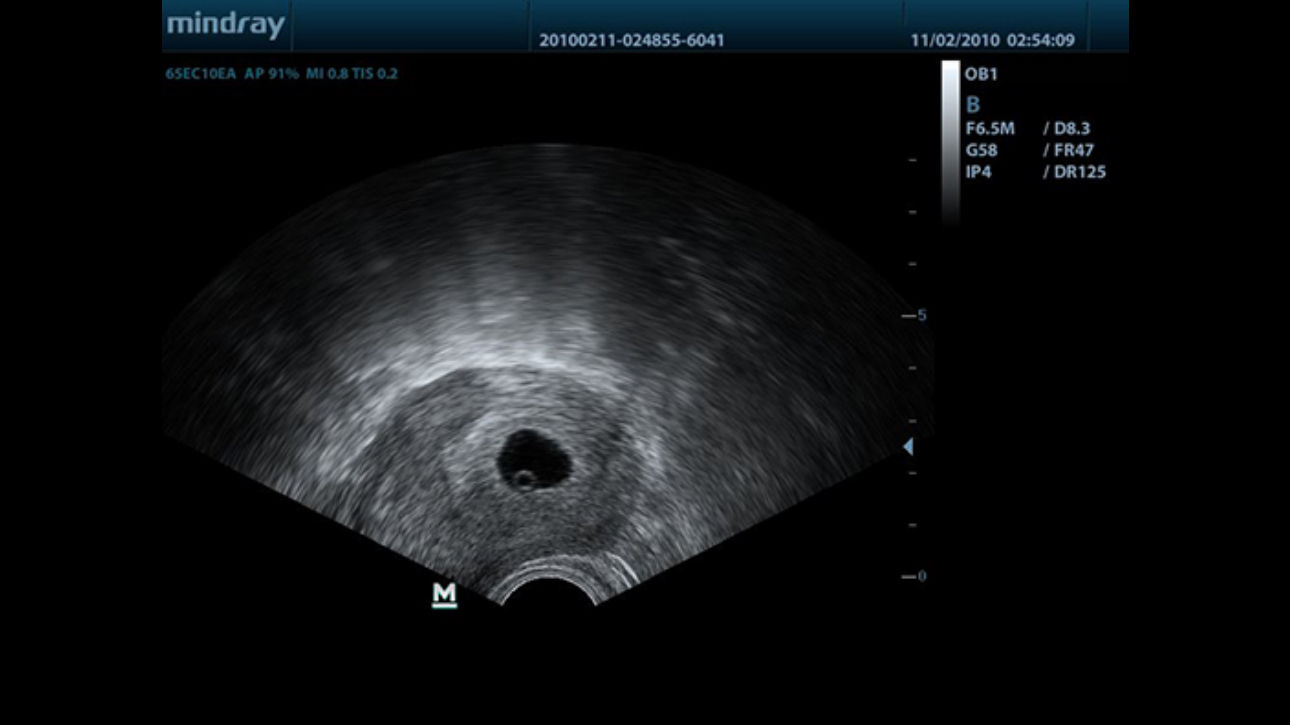

MindrayŌĆÖs new generation of black & white ultrasound system, DP-50, is equipped with advanced imaging technologies allowing deeper penetration and faster image acquisition with higher resolution.? A smart new shape, enhanced mobility and convenient operation make DP-50 well suited for all clinical settings.

Purified Harmonic Imaging for better contrast resolution providing clearer images with excellent resolution and less noise.

Permits use of multiple scanned angles to form a single image, resulting in enhanced contrast resolution and improved visualization.

Gain improved image quality based on auto structure detection.